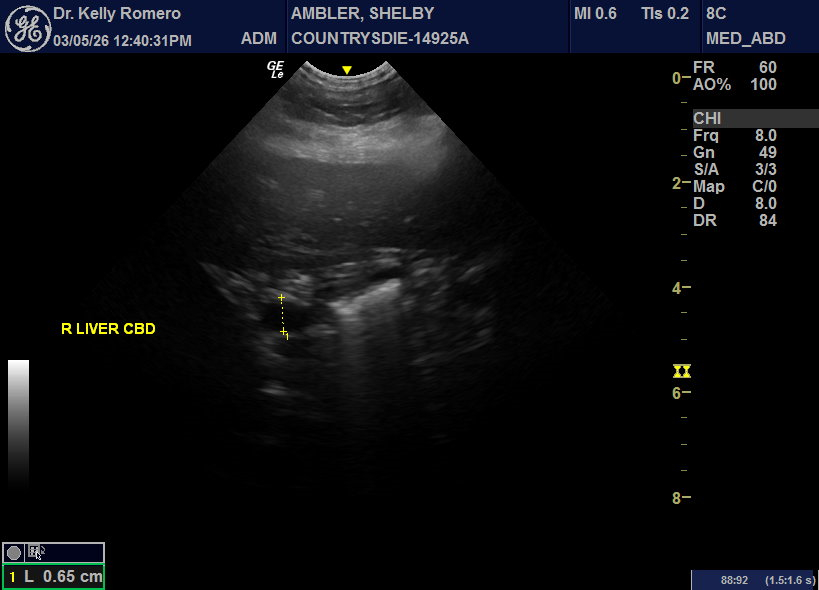

7 year 9 month old FS Chow with lethargy, vomiting and intermittently dribbling blood tinged urine. CBC WNL. Chem – ALT 773, ALP 389, GGT 31, T bili 0.5. Looks like choleliths in biliary tree, but focal region. No reported fever. Started Ursodiol, Denamarin, and antibiotics for cholangiohepatitis (Clavamox and metrondizadole). Urinary bladder looked unremarkable. There was a hyperechoic nodule in the otherwise normal left adrenal gland.

Rocks in the cbd… may need sx if she doesn’t pop them through the d-pap. Always scan right before cutting.to ensure the song remains the same 🙂

Hi Eric, thank you for taking a look! When I go back through, I can see where some of these hyperechoic choleliths could actually be in the gall bladder instead of outside of it – is there an artifactual phenomenon that causes them to look more like they are outside of the lumen at least in some views or do you think it is a combination of choleliths in the GB and the nearby tree?

Do you think medical treatment is an option in this case while monitoring LE (ursodiol, antibiotics) or best to refer for surgery? CBC looks empty to me, but distended – did I miss a stone in there?